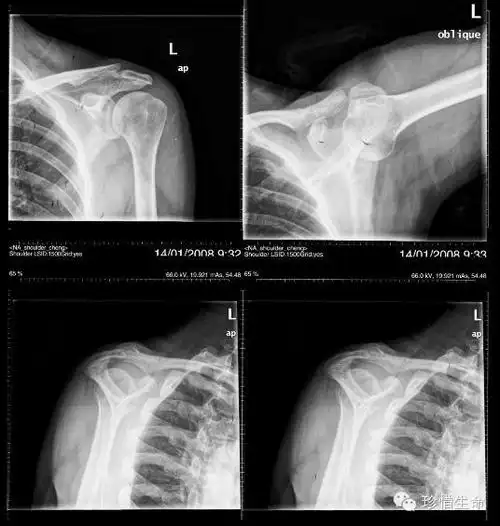

肩关节x线检查体位大全 - 好医术早读文章 - 好医术-赋能医生守护生命

肩部x线摄影-ppt参考课件